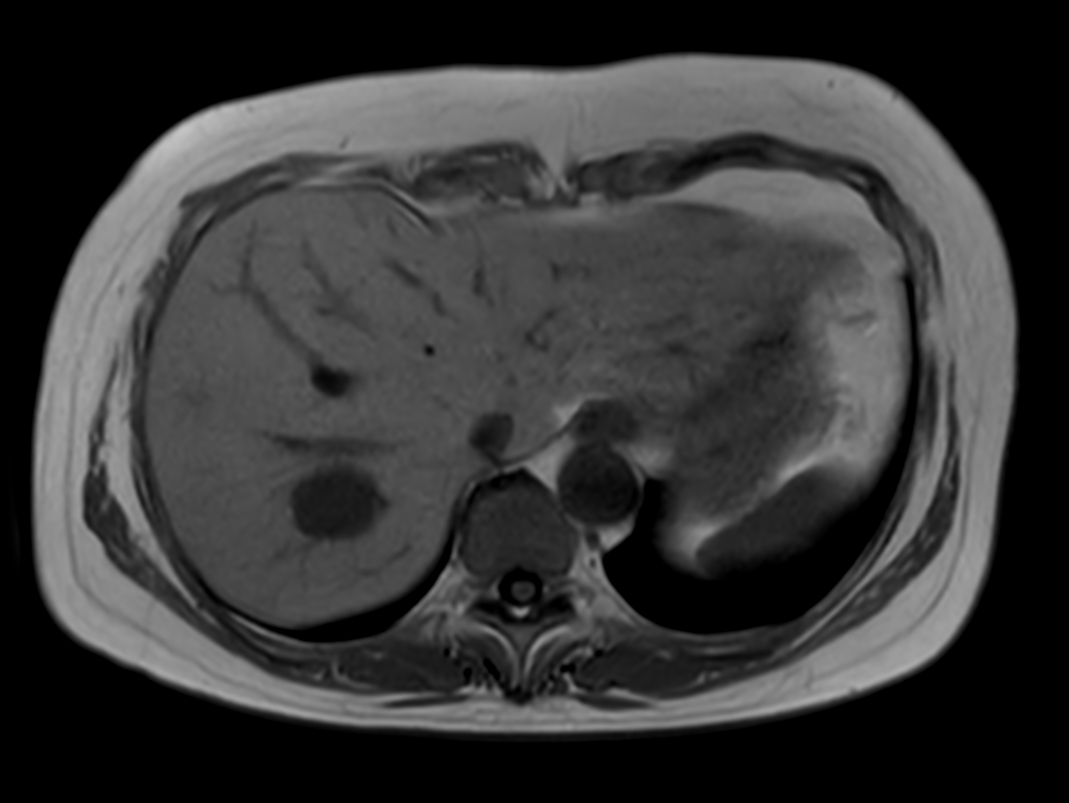

Axial T2w TSE